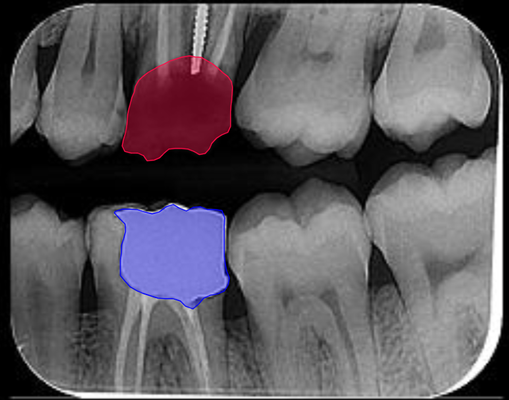

As the main product of Smartory startup, Smarteeth is a collaborative project with Shahid Beheshti Medical University, focused on developing an AI-powered assistant for diagnosing dental disorders using various radiography images (panoramic, bitewing, and periapical) and RGB images taken by mobile cameras. I was part of the core research and development team, where we collected and annotated over 100,000 radiography images and established a standard protocol for medical history and diagnosis forms in clinics. The AI tasks in this project include classification, detection, and segmentation of dental disorders, while Large Language Models (LLM) were used to generate basic diagnostic reports and basic suggestions based on the teeth condition. The project received significant attention at Exida, the International Congress of Dentistry, and has resulted in published research at the ICROM conference, with two more papers in progress. A free sample of our model is currently available on the Smarteeth website.